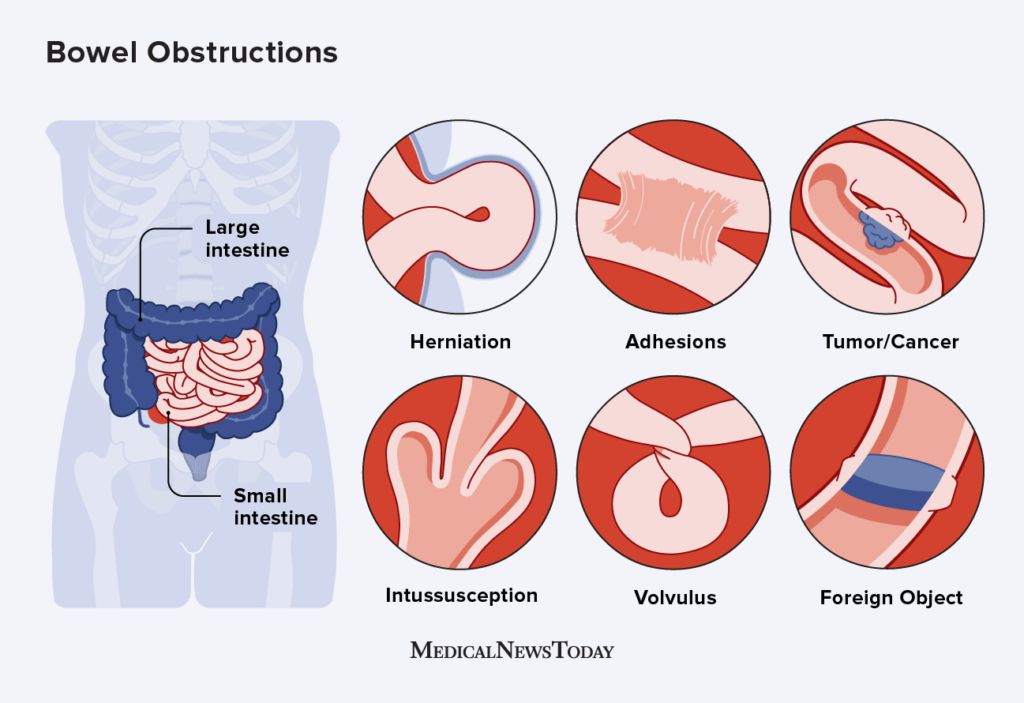

Bowel Obstruction Causes

Large Bowel Obstruction Bowel Obstruction Causes Management

Intestinal Obstruction

Intestinal Obstruction

Intestinal Obstruction